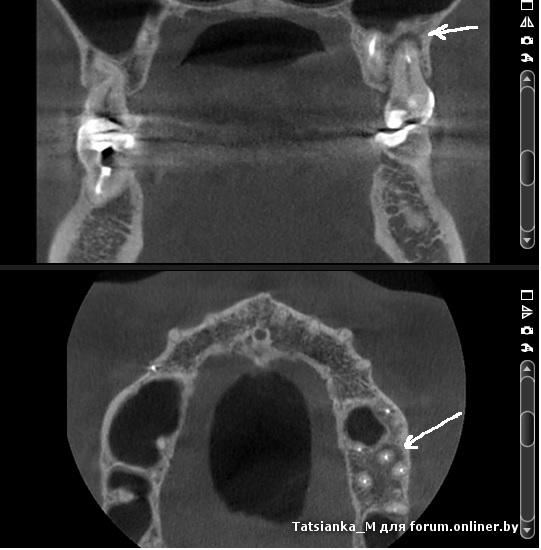

Новый врач и новое мнение по 27 зубу ретроградный периодонтит

Может быть такое? Белыми стрелками указаны зоны, которые вызывают подозрения у врачей.

Болит зуб хоть ты тресни!

Пока не лезли, болело непонятно где... залезли (сказали, нерв был нормальный), пошел отек на щеку, болело и на пломбировке каналов гуттаперчей (на снимке), болит и сейчас на кальции, причем на втором месяце "лечения кальцием" боль сильнее.

Стоит пальцем надавить на боковую стенку зуба, как возникает боль, потом начинает ныть... Если попробовать обхватить двумя пальцами зуб и покачать, то кажется что болит вся лунка и боль уходит кверху, и ощущение что зуб более подвижен, чем другие.

Или лечим не так, или зуб уже просто "не лечится"?

Ниже снимки с КТ ДО того, как начали лечение

(красная стрелка - гранулема на МЩК 26-го зуба, которую успешно полечили)

А вот кармана там нет, что бы он был ретроградный.